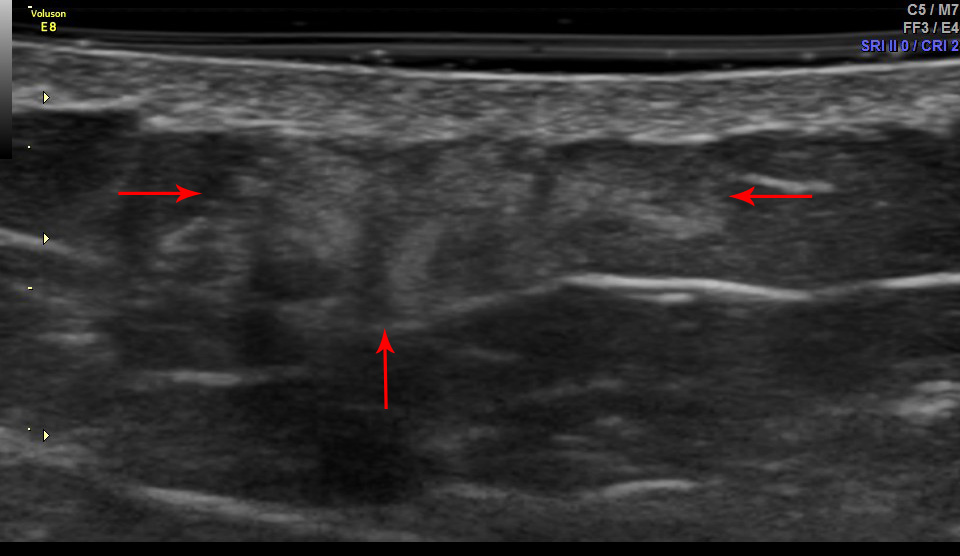

При ультрасонографии мест инъекций липогипертрофии выявлены у 80 (98%) пациентами, включая 25 с СД1 и 55 – с СД2. Cуммарная площадь участков липогипертрофий на передней брюшной стенке варьировала от 50 до 1847 мм2 (медиана 370 мм2). В большинстве случаев (91,5%) участки липогипертрофии характеризовались повышением эхогенности относительно неизмененной ПЖК (рис. 1). Медианы показателей MG1 и MG2 составили 37,8 и 29 соответственно, p<0,001. При исследовании в режиме компрессионной соноэластографии участки гипертрофии, как правило, демонстрировали большую жесткость по сравнению с неизмененной клетчаткой, при этом наблюдалось гетерогенное увеличение жесткости большинства образований (рис. 2). В режиме 3D-ангио обнаруживались гиповаскулярные зоны в области участков липогипертрофии (рис. 3), что подтверждалось при количественной оценке параметров кровотока (рис. 4).

Рис. 1. Гиперэхогенный участок липогипертрофии в подкожной клетчатке передней брюшной стенки в зоне инъекций инсулина у больного сахарным диабетом. Серошкальное сканирование в B-режиме.